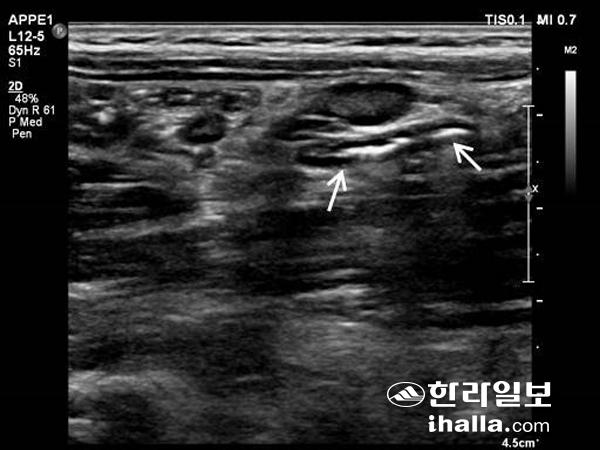

화살표 표시가 충수돌기.

초음파 영상을 실시간으로 보면서 간종양, 간실질, 췌장종양 등에 대해 조직검사를 할 수도 있고, 초음파 유도 하에 작은 간암에 대해 고주파열치료 같은 치료를 시행할 수도 있다. 비뇨기계 초음파의 경우 혈뇨, 옆구리 통증, 신기능 이상 등에 대한 원인 감별을 위해 시행하고, 신낭종이나 신결석 등의 추적 관찰에도 이용한다. 우하복부 통증의 경우 응급수술을 요하는 질환인 충수돌기염을 배제하기 위해 충수돌기 초음파를 시행하고, 하복부 통증 역시 소장 및 대장 초음파를 통해 원인을 찾아 볼 수 있다.

충수돌기 검사는 오른쪽 아랫배에 가장 아픈 곳을 직선 형태의 탐촉자를 이용해 누르면서 시행하게 된다. 검사가 끝나면 병원에 따라서 검사결과를 바로 알려 주는 경우도 있으나, 보통은 검사를 의뢰한 해당과 외래에서 결과를 확인하게 된다. 소요 시간은 숙달된 영상의학과 의사가 시행하고 큰 이상 소견이 없는 복부 초음파검사는 10분 이내에 검사를 끝날 수 있지만 복잡한 상복부 초음파검사나 도플러검사가 필요한 경우, 충수 초음파검사의 경우에는 소요 시간이 훨씬 길어지기도 한다. 검사가 끝나면 젤리를 닦고, 이후에는 바로 일상 생활을 할 수 있다.